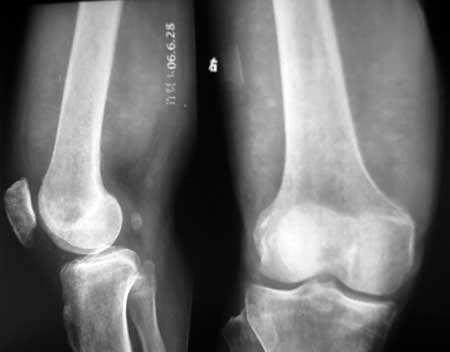

男56涨疼5-6月

右股骨下端包绕股骨见巨大软组织肿块,密度部俊,周围见瘤骨,下端骨皮质侵蚀变薄,骨质周围无骨膜反应, 考虑右股骨软骨肉瘤。

右股骨下段周围软组织肿块伴钙化,相邻股骨骨皮质受累,考虑软组织来源恶性病变

右股骨下段骨肉瘤,软组织内瘤骨,软组织肿块。